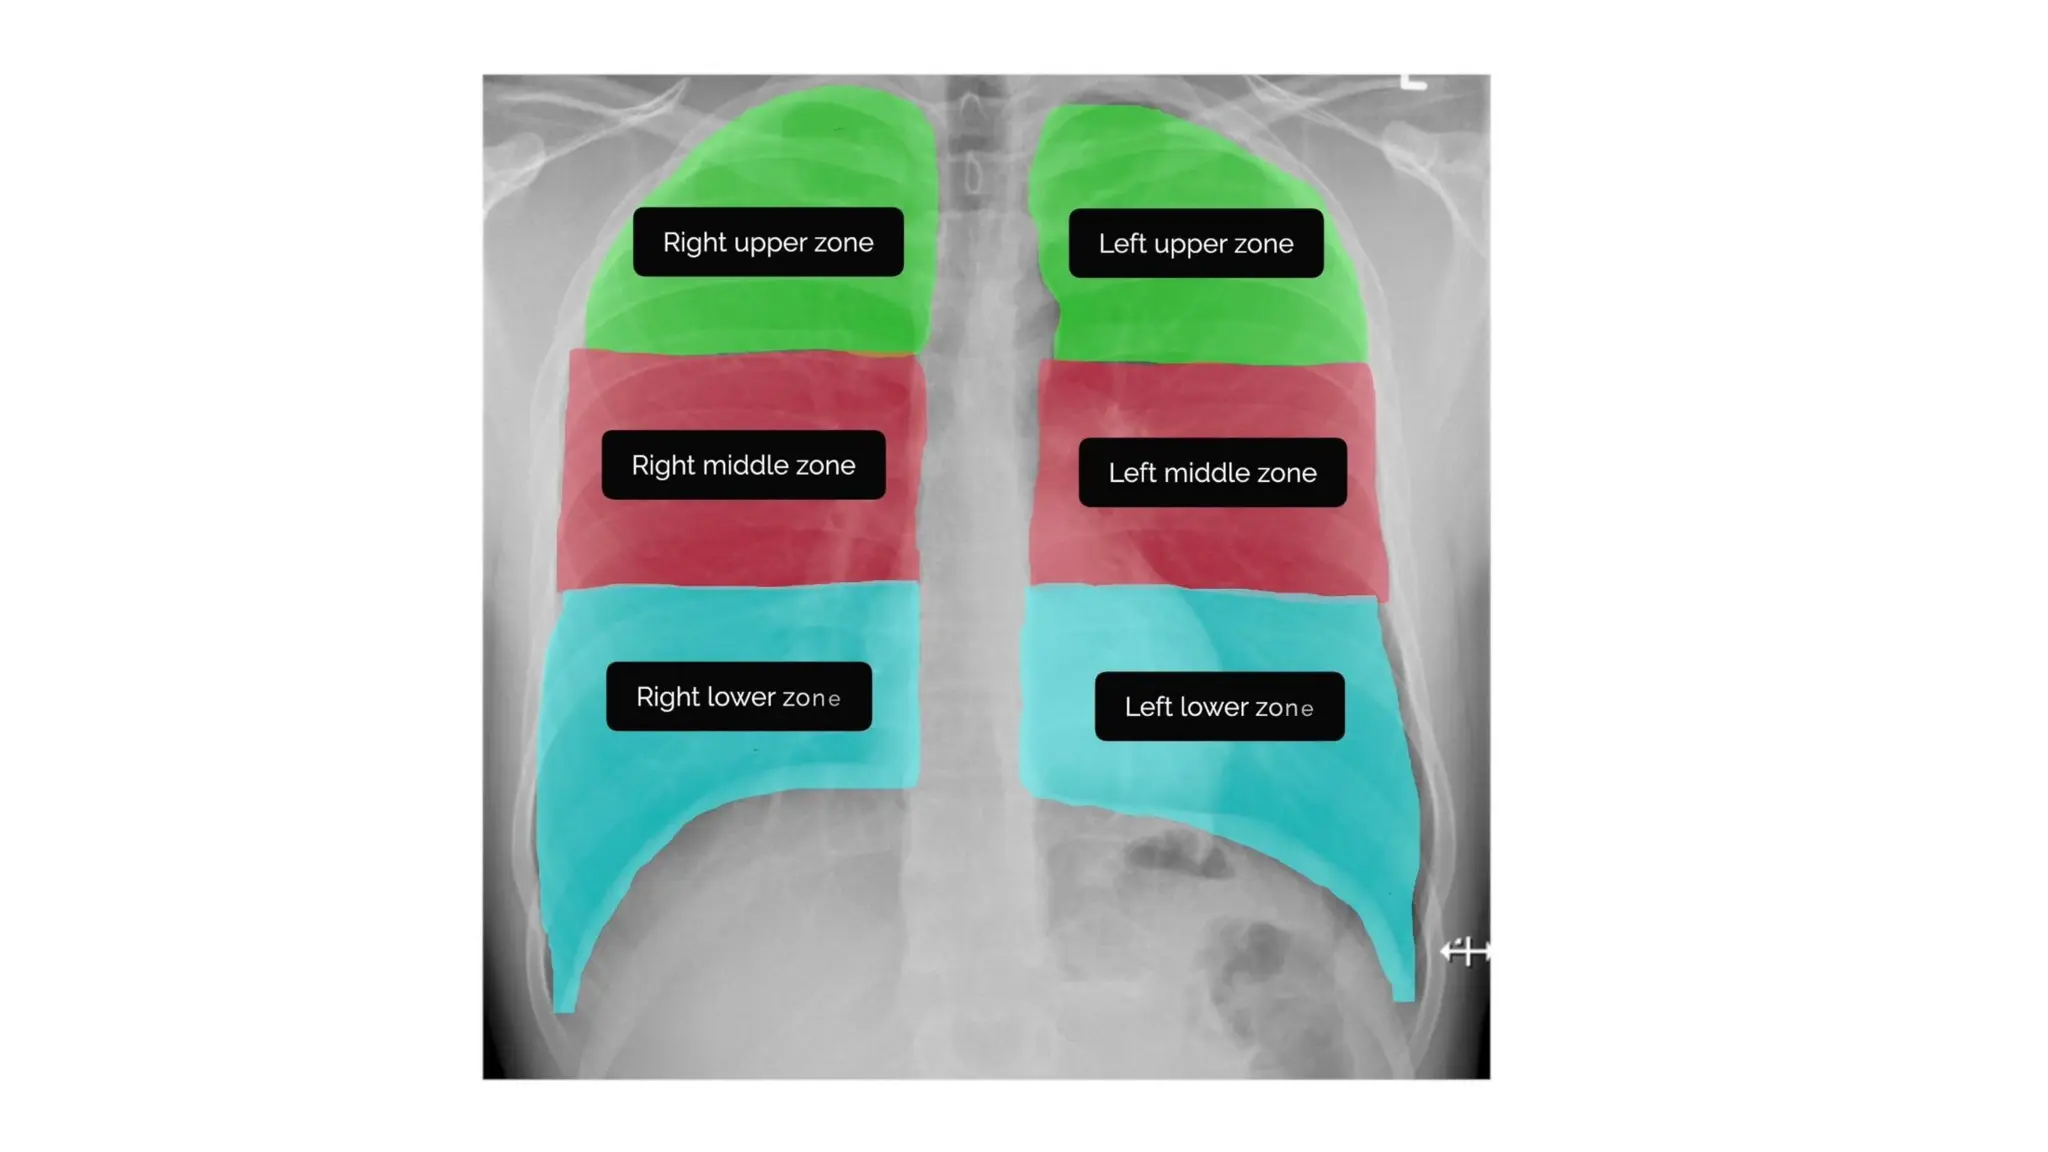

Breathing

• Divide each of the lungs into three zones & inspect each zone,

noting any asymmetry.

Breathing • Divide eachof the lungs into three zones & inspect each zone, noting any asymmetry.